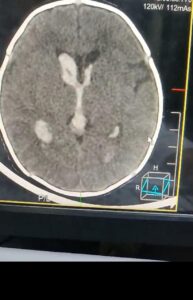

عملية نادرة تنقذ رضيعة عمرها 20 يومًا من نزيف بالمخ في مستشفى دمياط العام

السيد السيد خميس